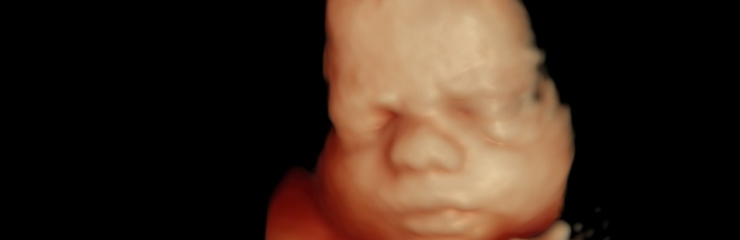

Шейные позвонки хорошо видны. На 23-й неделе плод весит примерно 550 граммов. С 23-й недели на 4D-ультразвуковом исследовании уже можно хорошо рассмотреть черты лица плода.

- По желанию — 4D-ультразвуковое исследование (24–32 недели)

Вес плода составляет примерно 1 килограмм, длина — около 35 сантиметров. Это лучшее время для наблюдения лица плода с помощью 4D-ультразвукового исследования.

Это время, когда стоит постепенно начинать думать о родах и обсудить, кого женщина хотела бы видеть в качестве сопровождающего на родах. В этот период можно вместе сходить на 4D-ультразвуковое исследование, которое даёт информацию о здоровье и развитии ребёнка, а также позволяет будущим родителям наблюдать за своим малышом в реальном времени, вызывая радость и положительные эмоции.